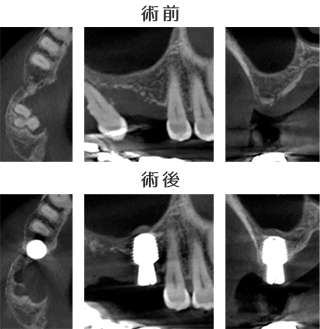

術前CT画像において、右上6欠損部は垂直的な骨の厚みが最薄部で3mmでした。

従来であれば骨補填が必要となり、上顎洞挙上術(サイナスリフト)などを併用し、治療期間は10か月に及ぶ症例です。

しかし当院のインプラント治療は、ワイドショートインプラントを用いることで骨補填を行わず、インプラント埋入手術を行います。

インプラントはMegaGen φ6.0×7.0mmを選択し、1回法での手術としました。

インプラントの位置、深さ、方向、いずれも予定通りに埋入し、サイナスリフトなど骨補填は行いませんでした。

インプラント埋入手術から上部構造(インプラントのかぶせもの)装着まで、良好な経過をたどり、埋入手術~治療完了までの治療期間は10週でした。